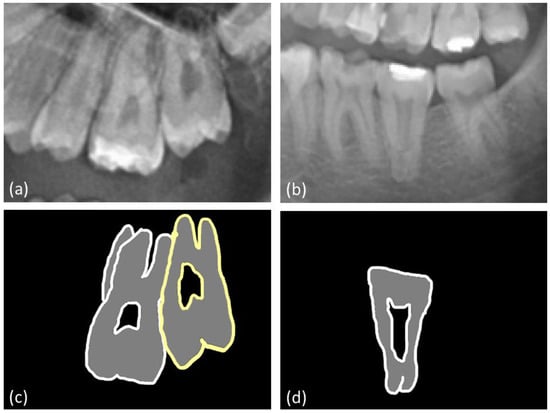

2.3. Measurements